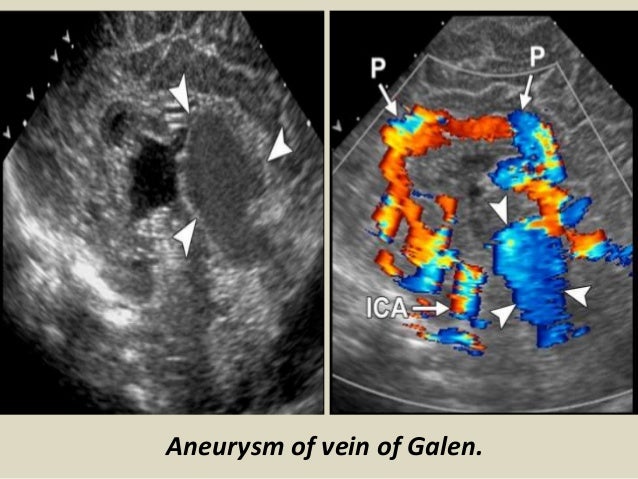

27. 27. Aneurysm of vein of Galen.

28. 28. Gray-scale and Doppler coronal USG demonstrating a cystic midline structure in the region of posterior third ventricle with mass effect. (A) Typical swirl effect is noted on Doppler (B). Findings are highly suggestive of aneurysmal malformation of the vein of Galen. The corresponding axial and sagittal T2W images of MR examination confirming large aneurysmal dilatation of the vein of Galen (C and D)